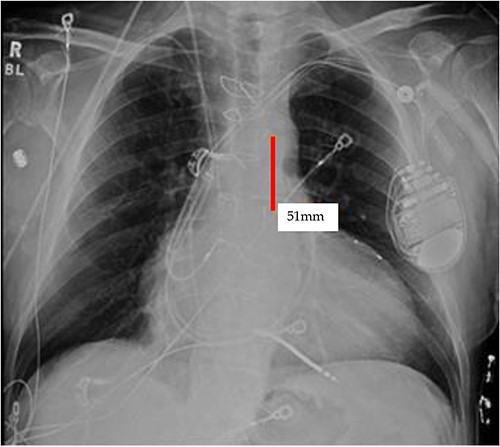

It appears that the IABP became mispositioned after its initial placement as seen on follow-up CXR (Fig. 4). Despite almost daily CXRs, this IABP mispositioning was missed by the managing team and radiologists, probably due to interference from the automatic implantable cardioverter defibrillator (AICD) leads, EKG leads, and sternal wires. Twenty-one days later (Fig. 5), the radiologist erroneously read that the IABP had been removed, so CXRs were never repeated. Figure 5 shows that the IABP was still folded over itself but now with a shadow in the arch/ascending aorta from the migrated IABP.

CXR done 21 days later, which shows the markers still not properly placed but the distance is about the same (5.8 centimeters) as the original position; additionally, the shadow of the inflated helium balloon can be seen in the ascending and aortic arch.